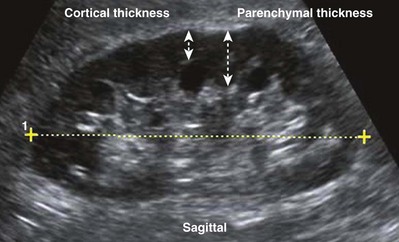

Renal size changes over the lifetime of an individual. Nomograms for pediatric renal size should be consulted. These are based on age, height, and weight of the patient. The average adult kidney measures 10 to 12 cm in length and 4 to 5 cm in width. Measurements of renal volume may be appropriate in cases of severe renal impairment. Renal measurements should be obtained in the midsagittal plane and midtransverse plane. Measurements taken in other than the midsagittal plane and midtransverse may be spuriously low. The thickness of the parenchyma is the average distance between the renal capsule and the central band of echoes. The precise location for making this measurement is somewhat subjective. The midlateral renal parenchyma in the sagittal view is a common choice for obtaining this measurement (Fig. 4–33). Although there is no universal standard, the renal cortical thickness should be greater than 7 mm (Roger et al, 1994), and the renal parenchymal thickness should be greater than 15 mm in adults (Emamian et al, 1993b).

Figure 4–33 The distinction between renal cortical thickness and renal parenchymal thickness is that the renal parenchyma is measured from the central band of echoes to the renal capsule. The renal cortex is measured from the outer margin of the medullary pyramid to the renal capsule.